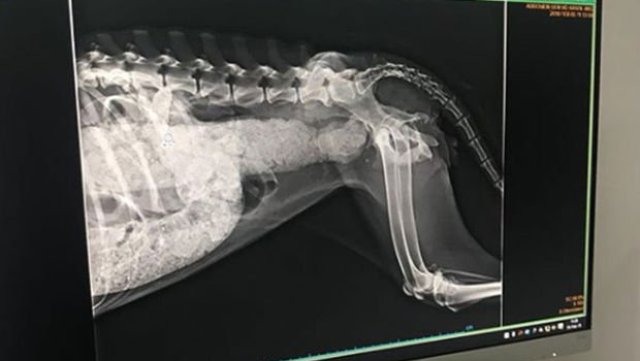

Veterinere götürülen köpeğin röntgen sonuçlarında, bağırsaklarının tamamen silikonla doldurulmuş olduğu görüldü. Klinik'ten yapılan açıklamada köpeğin tedavi sırasında hayatını kaybettiği belirtildi. Öte yandan köpeğin kurtarılması için yardım eden işçilerin tinercilerin silikon sıktığını söylediği iddia edildi.

Kadınlar tarafından veterinere götürülen köpeğin röntgen sonuçlarında bağırsaklarının tamamen silikonla doldurulmuş olduğu görüldü. Makatından sıkılan silikon nedeniyle yemek yiyemeyen ve dışkı yapamayan köpek ameliyata alındı.

'Coffee 2 haftadır @eceaykultas ve @watdirivizzik in peşinde olduğu bir köpekti. İskeleti çıkmış, 10 adımda bir kaka yapmaya çalışıp yapamayan genç dişi bir köpek. Yaptığı kaka da zift gibi, kanama var. Yakalanmasına yardım eden işçiler tinercilerin silikon sıktığını söyledi! Bugün çekilen röntgende bağırsakların komple dolu olduğu görüldü. Röntgeni sola kaydırarak görebilirsiniz. Doktorumuz elle muayene etti, içerisi taş gibi olmuş! Ne yemek yiyebiliyor, ne kaka yapabiliyor. Yaşaması resmen mucize!! Bu akşam operasyona girecek, kalın bağırsaktan bu illet nasıl temizlenir bilmiyoruz dua edin. Karaköy'deki köpekler büyük tehlike altında, lütfen artık bir şeyler yapın. Coffee'de çok ciddi bir enfeksiyon var aynı zamanda. Şu anda toksoplazma tedavisi görüyor, tedaviye verdiği cevaba göre daha güzel gelişmeler aktaracağız inşallah size.'

Köpeğin tedavisiyle ilgilenen klinik tarafından köpeğin tüm müdahalelere rağmen kurtarılamadığı belirtildi. Ameliyat sonrasında kalın bağırsağının temizlendiği yemek borusunun delinerek sonda takıldığı ancak köpeğin tedavi sırasında hayatını kaybettiği belirtildi.